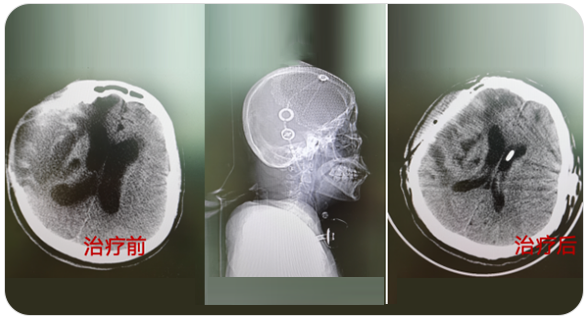

精通颅内动脉瘤介入栓塞和手术夹闭双技术,系统掌握脑动静脉畸形、颈内动脉海绵窦漏、硬脑膜动静脉漏等颅内血管疾病的诊疗和手术,精通颈动脉、椎动脉狭窄的血管内重建技术,以及颈动脉狭窄的内膜剥脱手术技术。在颅内肿瘤、椎管内肿瘤、颅脑损伤、高血压脑出血等疾病的诊治和手术,脑功能性疾病立体定向手术治疗等方面也积累了丰富的经验。

擅长脑血管病(出血与缺血)的神经介入与微创手术,能熟练开展脑外伤、重度颅脑损伤的救治工作。